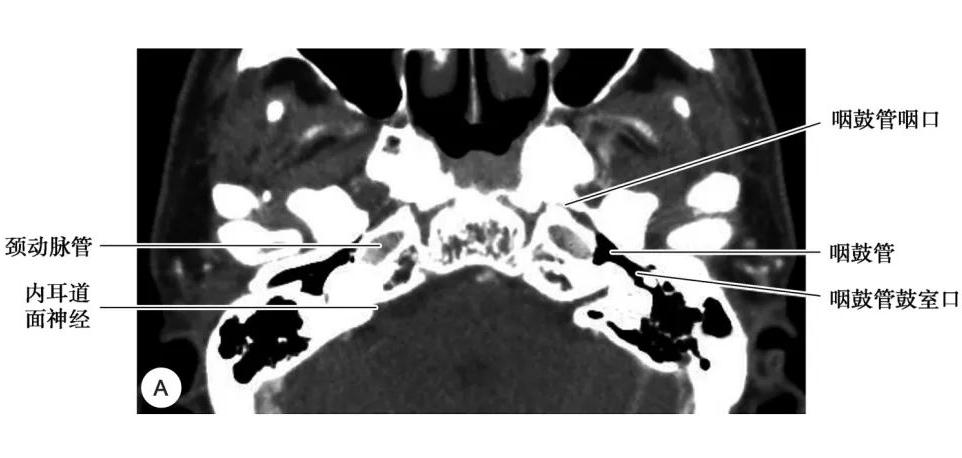

咽鼓管结构

A. CT;B. MRI

2.咽鼓管

咽鼓管为连接鼻咽腔与鼓室的通道,向内通鼻咽腔,开口于咽鼓管咽口,向外通鼓室前壁,开口于咽鼓管鼓口,鼻咽癌可经咽鼓管侵入中耳。